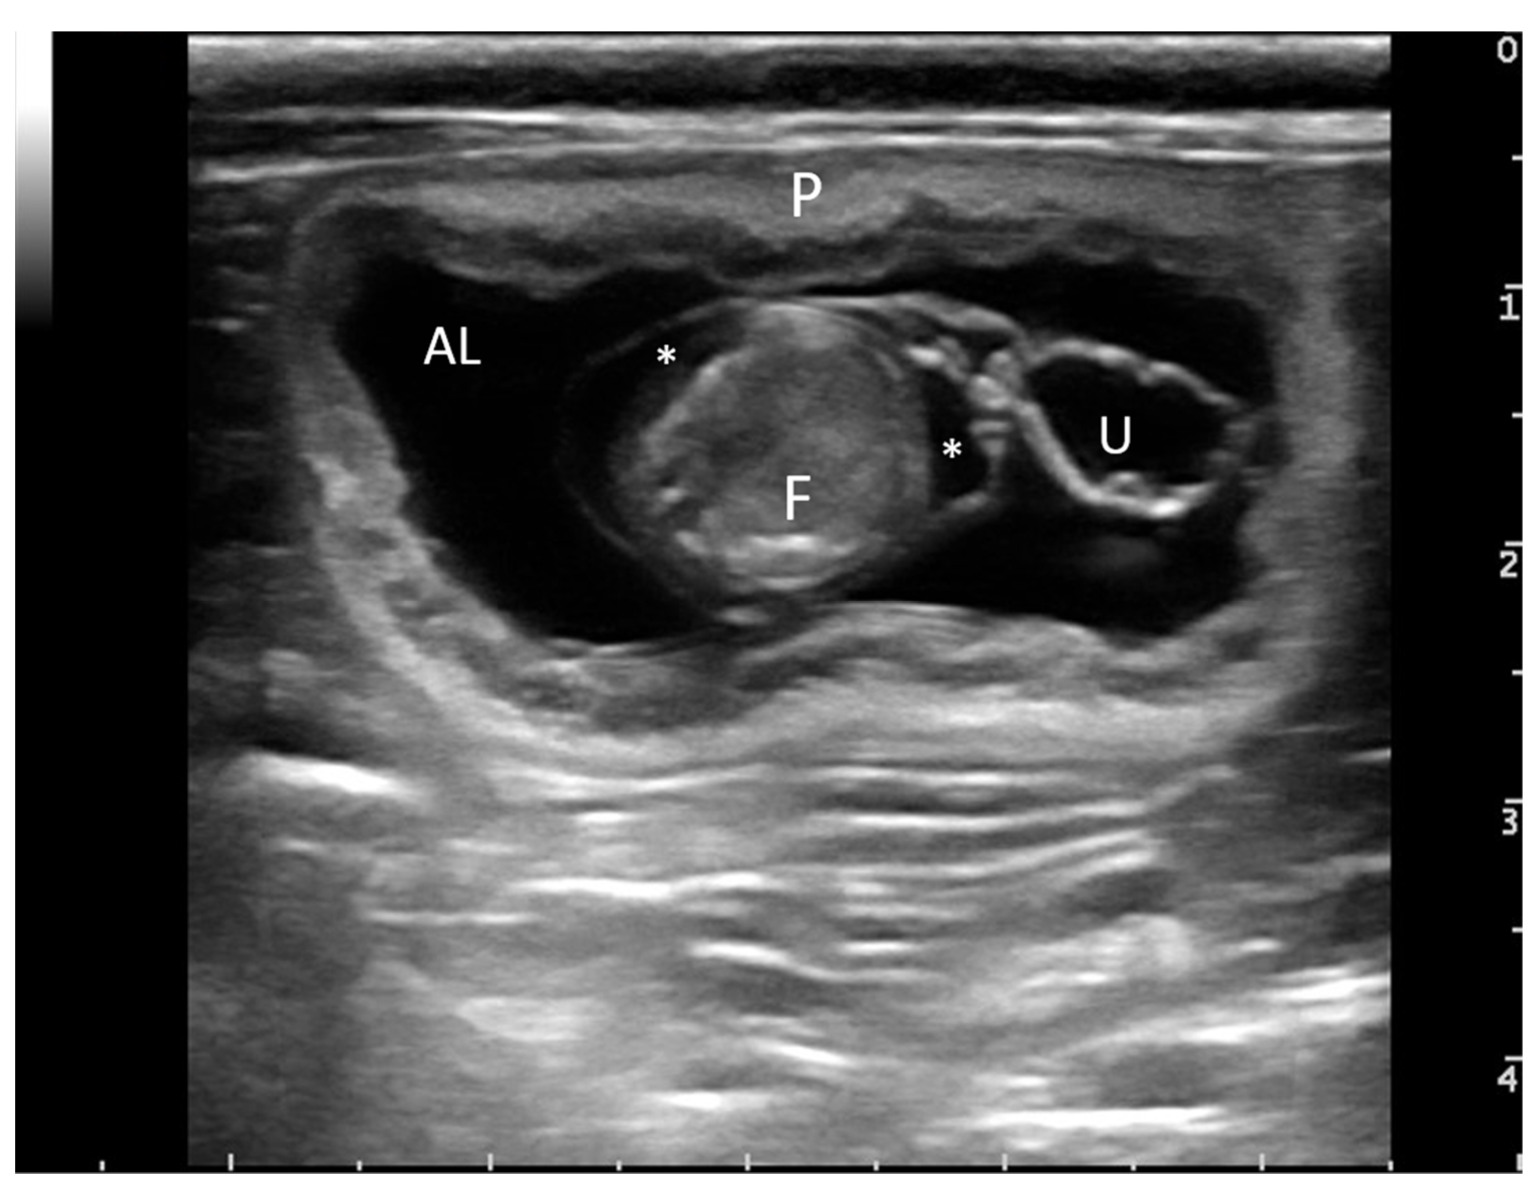

2.2. Surgical Procedure

2.3. Sample Collection